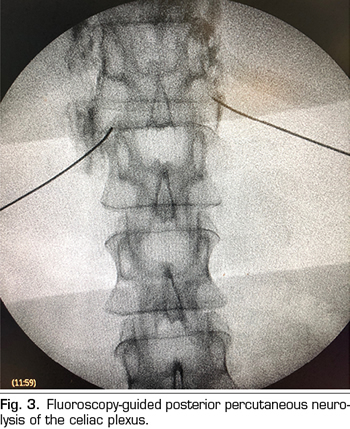

Transcrural approach: the most commonly used for the blockage of the celiac plexus (Figure 3). The patient is placed in prone position, identifying the vertebral body L1 and advancing a needle on each side, approximately 7.5 cm from the midline, until it crosses the diaphragmatic crura and blocks the plexus.